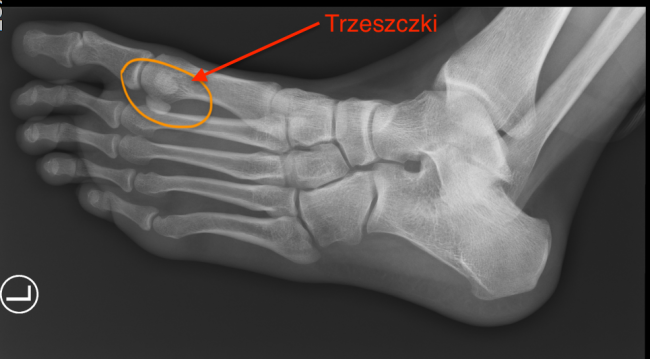

Trzeszczki – czym są? Jak leczyć choroby trzeszczek?

Trzeszczki – czym są? Jak leczyć choroby trzeszczek? Bóle stopy związane z chorobami trzeszczek bardzo często nie są właściwie diagnozowane. Trzeszczki to drobne kostki w stopie (aczkolwiek występują nie tylko tam), które wspomagają pracę stopy. Występują w liczbie dwóch (trzeszczka piszczelowa i strzałkowa) w okolicy stawu śródstopno-paliczkowego palca I (ang. metatarsophalangeal joint – MTPJ), czyli…